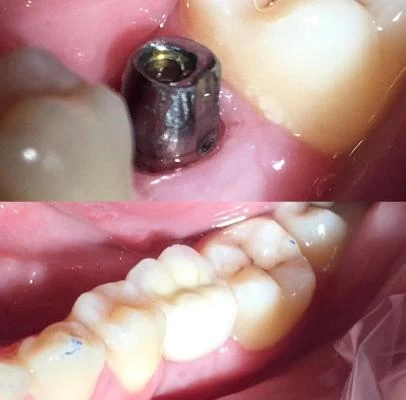

الدكتور فتح اله عباسپور طبيب أسنان

مجال النشاط الدكتور فتح اله عباسپور طبيب أسنان